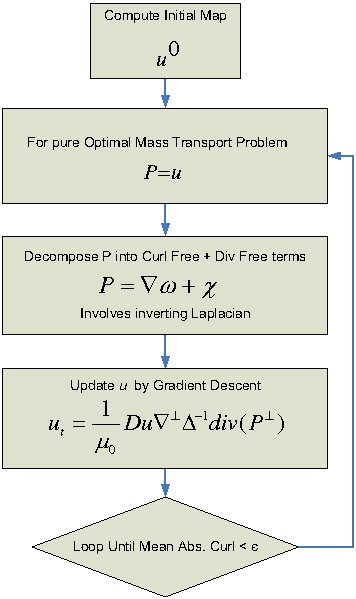

The flowchart of the algorithm is shown in the following figure.